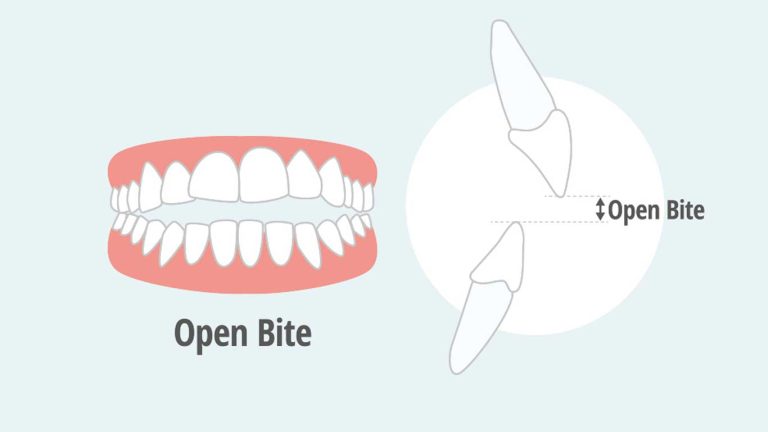

پاسخ: بله، لکه های سفید همانطور که گفته شد، اولین نشانه پوسیدگی دندان هستند. اگر این فرآیند متوقف نشود، لکه سفید به یک حفره واقعی تبدیل خواهد شد که نیاز به ترمیم (پر کردن) دارد. بنابراین، هرگونه تغییر رنگی باید جدی گرفته شود و به عنوان یک زنگ خطر برای بهبود فوری بهداشت دهان تلقی گردد. انواع بایت های دندانی نادرست، زمینه ساز این مشکلات بهداشتی است.